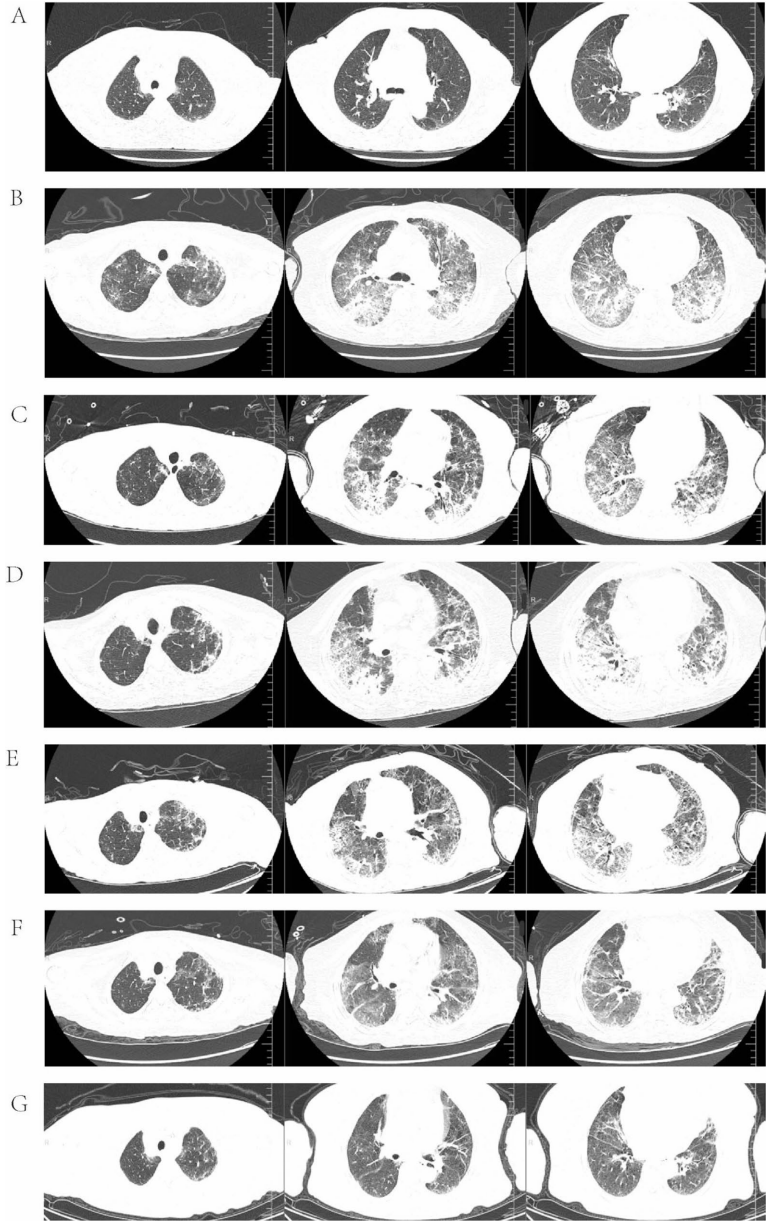

),采用80mg甲基强的松龙联合静脉免疫球蛋白的强化方案,最终实现肺部病变显著吸收(

)。